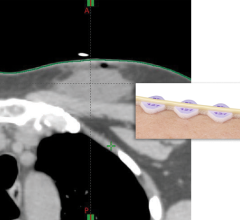

The radiology imaging channel includes technology news related to computed tomography (CT), digital radiography (DR / X-ray), ultrasound, magnetic resonance imaging (MRI), radiographic fluoroscopy (R/F), mammography, angiography, 3-D printing, contrast media injectors, molecular imaging, neurological imaging, pediatric imaging and radiation dose management.